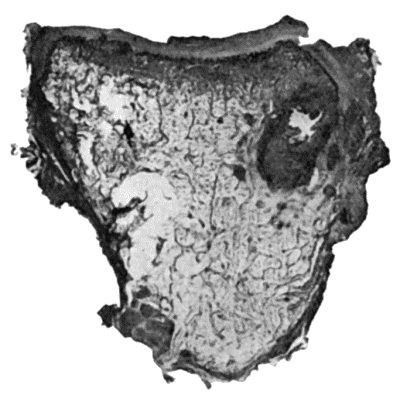

427 114.Section through Gouty Bursa

428 115.Tuberculous Disease of Sub-Deltoid Bursa